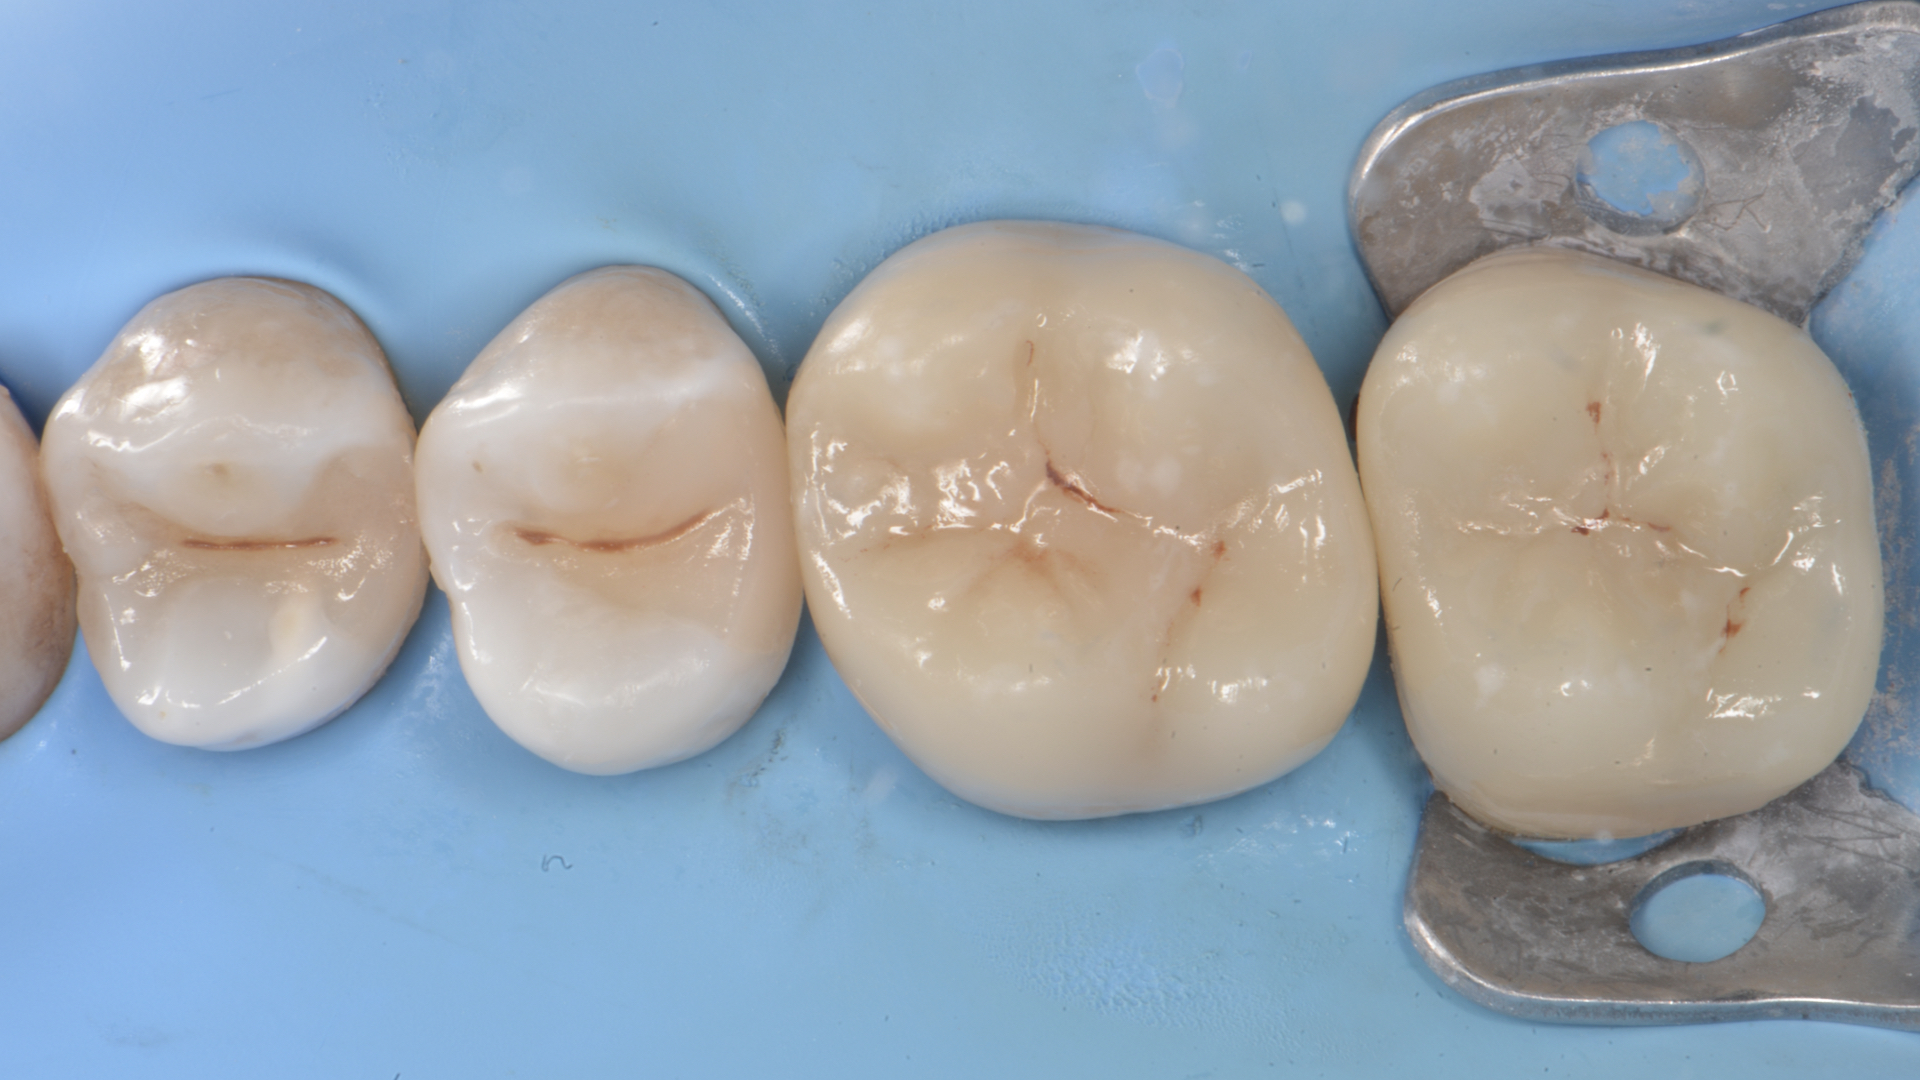

Figure 5. Restoration of distal wall 1.5 (Garrison Composi-tight 3D Fusion System)Figure 6.  Restoration 1.4-1.5 completed. Final Preparations 1.6 -1.7

Figure 7.  Impression (Sandwich technique)Figure 8. Master cast. Hybrid Ceramic overlays. (ODT Alessandro Morelli)